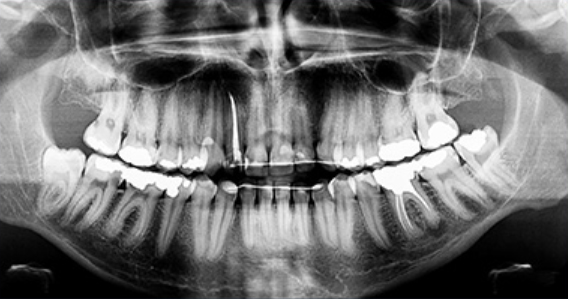

사랑니 충치

사랑니는 어금니 뒤쪽에서 나오는데

사랑을 느낄 만한 나이인 10~21세쯤 에 난다고 해서 사랑니라고 부르며

다른 명칭으로는 세번째 나는 큰 어금이라고 제 3대구치라고 불립니다.

가장 안쪽에 있는 사랑니는

칫솔이 잘 닿지 않아 관리가 안되어서

충치나 잇몸 질환이 생기기 쉽습니다.

비정상적인 위치에 매복되어 자란 사랑니는

염증과 통증을 일으킬 수도 있으므로

발치하는 것이 좋습니다.

누워서 자란 사랑니의 경우

바로 앞의 어금니 뿌리를 압박해 염증을 일으키거나

턱뼈의 신경까지 손상시킬 수 있습니다.

사랑니와 어금니 사이에 음식물이 끼게 되어 충치 및 치주염 발생의 위험율이 높아집니다.

매복된 사랑니는 3D 첨단 CT촬영으로 상태를 정밀검사하고 발치계획을 세웁니다.

사랑니 발치 시에는 뿌리가 신경관과 근접해 있는지 또 어느쪽으로 휘어져 있는지를

파악해야 훨씬 더 안전하고 편하게

또 빠르게 뽑을 수 있습니다.

최첨단 3차원 CT를 이용하여 사랑니 뿌리의 위치와

신경관 위치 등을 정밀하게 분석한 후 시행하고 있습니다.